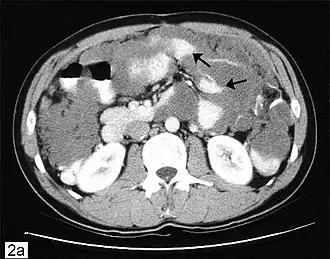

Lors de la ponction, on retrouvera un liquide très dense, riche en protéines (liquide exsudatif), très difficile à évacuer. Au scanner ou à l'échographie, le pseudomyxome est le plus souvent cloisonné. On observe des encoches au niveau hépatique et/ou splénique, très évocatrices de la maladie.